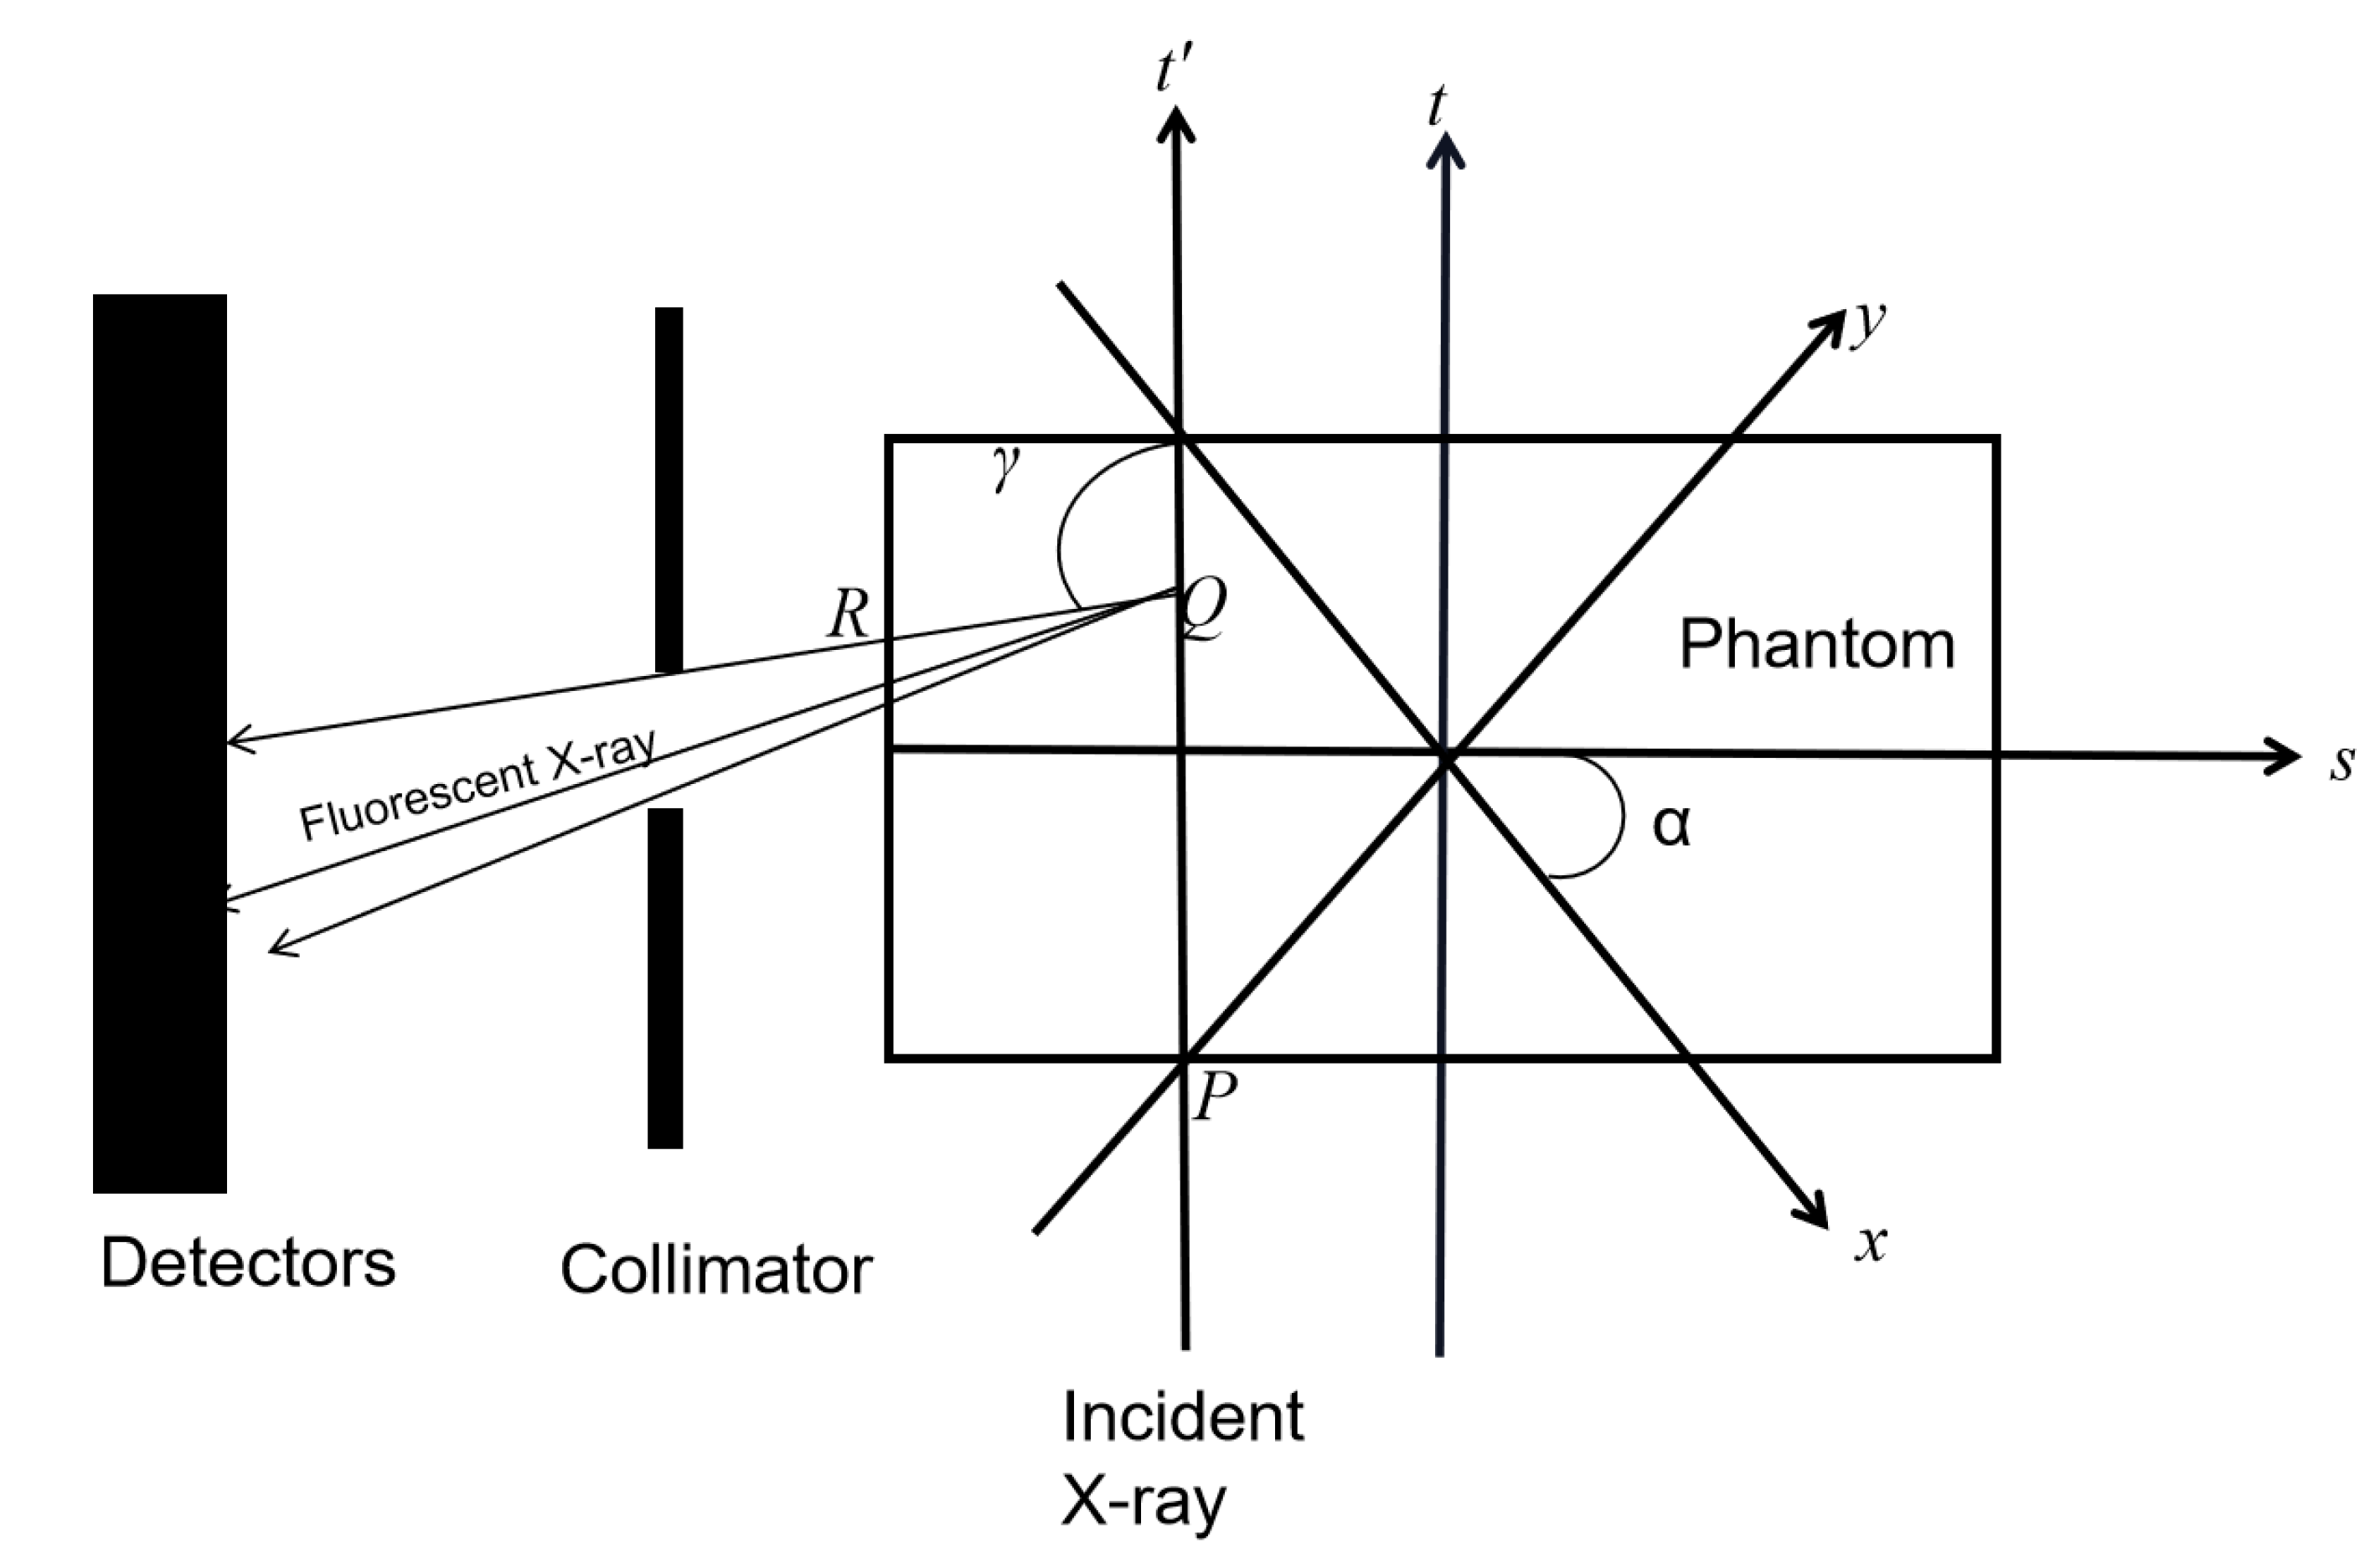

2.1. XFCT Theory